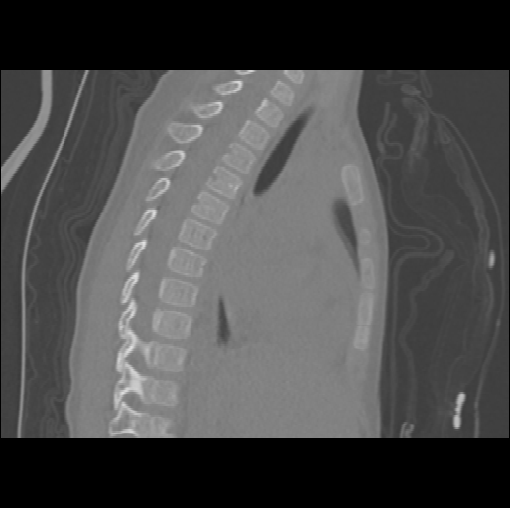

Spinal imaging via computed tomography (CT), magnetic resonance imaging (MRI), radiography, ultrasound, positron emission tomography (PET), and other radiologic imaging modalities is essential for noninvasively visualizing and assessing spinal pathology. Computational methods support and enhance a physician’s ability to utilize these imaging techniques for diagnosis, noninvasive treatment, and intervention in clinical practice. Analysis algorithms developed in the field of computer vision, computer graphics, signal processing, and machine learning have been adapted to analyze spinal images (Li et al., 2015). Conventionally, CT is preferred to study the spine due to a high bone-soft tissue contrast. There are diverse image appearance variations due to differences in vertebral position, metal artifacts and spinal diseases, etc., challenging the analysis algorithms. Fig. 1 gives some examples of these various conditions.

We calculate the two metrics of each vertebra, and the results are reported in Table 2. On the one hand, our experimental results are close to those reported in reference (Sekuboyina et al., 2020) with the same model (nnUnet), verifying the high quality of our annotations. On the other hand, Table 2 shows it is difficult to segment the diseased vertebrae (the DSC of L6 is almost 0). Specifically, the existence of L6 confuses the model, resulting in prediction dislocations (see the last row in Fig. 4). Thus, our labeled dataset, which contains many L6 cases, is very valuable for the diseased vertebrae segmentation (we have stated those cases that are hard for annotation in the readme.txt file). Table 2 illustrates that the model trained with our annotations can achieve good performance on our CTSpine1K dataset but a much worse performance on the VerSe Challenge datasets, which explains there is an obvious domain gap between our annotated dataset and the public dataset. We infer the reason is that the COlONOG dataset is based on an empty stomach and colon, confusing the deep learning model by the changes of air content in the abdomen (see Fig. 3). Therefore, our annotations are a good complement to the existing datasets.

3.2.2 Qualitative results.

Some visualization results are presented in Fig. 4, where we can observe that the baseline model can achieve excellent segmentation results. Nevertheless, some failed predictions occur when spinal diseases exist, especially sacral lumbarization and lumbar sacralization. Besides, the image’s resolution of Z direction is closely related to the results, and a lower resolution leads to worse results. Maintaining a reasonable performance for a low resolution is a research challenge. Image superresolution (Peng et al., 2020) might be worth exploring.